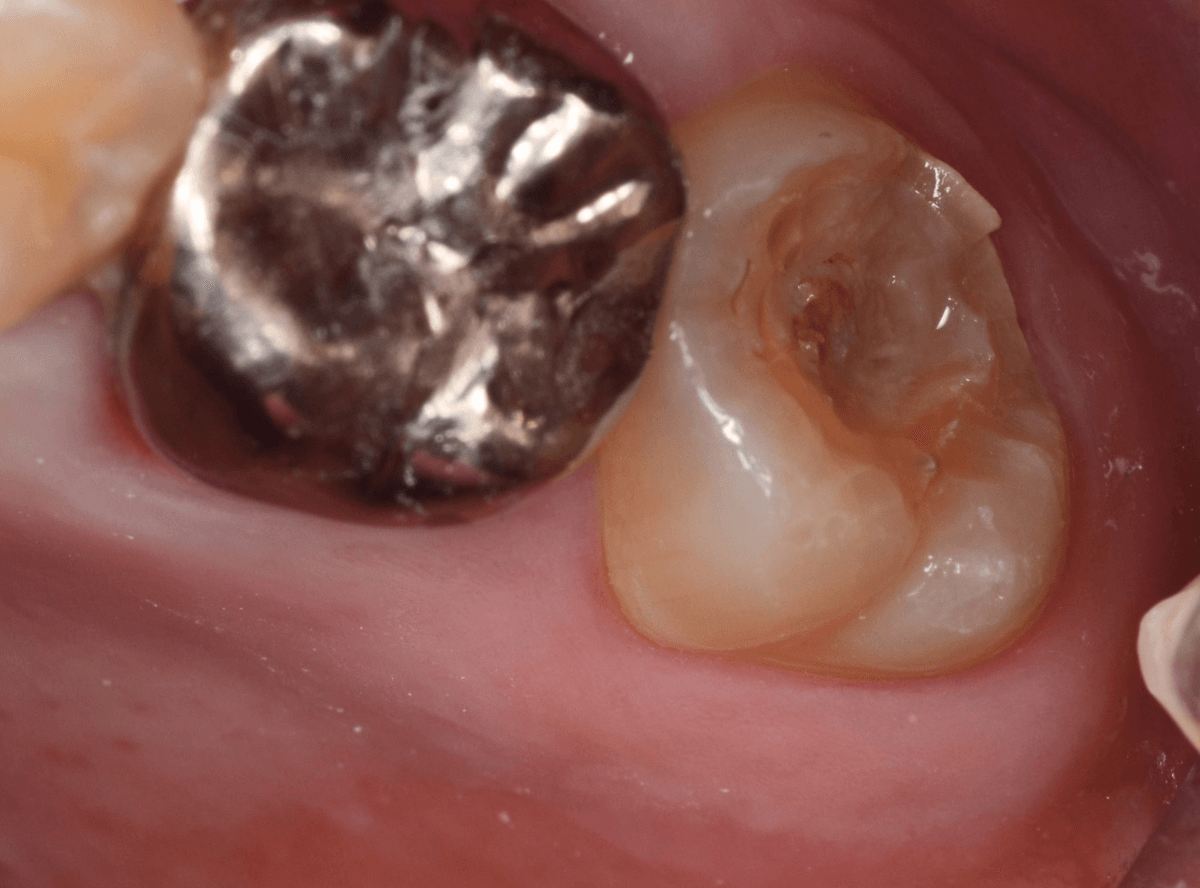

「下の一番奥の歯が痛い」という訴えで来院された患者さんの例です。

一見では、特に問題ないように見えます。

レントゲン写真で確認します。

青いラインが歯の神経、赤いラインが虫歯です。

歯の奥の見えない部分から、大きな虫歯になっているのがわかります。

神経を除去しなければいけないかもしれないくらいの虫歯です。

治療を開始します。

歯の奥の部分を少し削ると、虫歯が出てきました。

慎重に虫歯を除去します。

歯肉ラインの下まで虫歯が進行しているため、虫歯の上に歯肉が広がっており、虫歯の見分けがつきづらい状況になっています。

虫歯を取り残さないように、余分な歯肉を除去します。

電気メスで、虫歯周囲の歯肉を除去後、全ての虫歯を除去しました。

虫歯は深かったですが、なんとか神経寸前のところで食い止められました。

神経を保護するお薬をつめて、セメントで蓋をしてしばらく経過観察します。

経過観察後、痛みがない事が確認できれば、つめものを作製します。